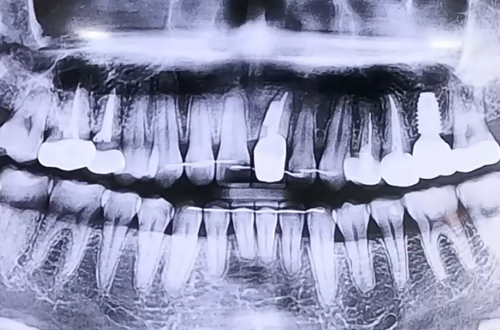

BEFORE

치료 유형 어금니 임플란트, 앞니 충치 치료

본래 저희 병원에서 어금니 임플란트 치료를 진행하고 계셨던 환자분으로 치아와 잇몸의 상태 등 여러 조건이 양호해서 어렵지 않게 임플란트 하고 계셨던 분입니다.

임플란트 식립 후 굳을 때까지 4개월을 기다리면서 경과를 보기 위해 내원해 검사를 받게 되는데요.

검진을 위해 오신 환자분께서, 얼마전부터 앞니에 염증이 생기고 붓는다고 앞니 검사를 해 보고 싶다고 요청을 해 주셨습니다.

그래서 불편해하시는 앞니를 정밀하게 검사해본 결과, 이전에 보철치료를 했던 앞니 부분의 안쪽에 충치가 발생했고, 그 충치를 중심으로 겉으로 염증이 발생한 상태로 보였습니다.

이렇게 안쪽에 생긴 염증이 바깥쪽으로 빠져나갈 통로가 없어서 잇몸이 붓고 터지는 것인데요.

치아는 그대로 살리면서 안쪽 충치를 치료한 뒤 염증을 깨끗이 긁어내고 잇몸을 닫는 치주 수술을 진행해드리며 임플란트 역시 함께 마무리 해 드렸던 케이스입니다.